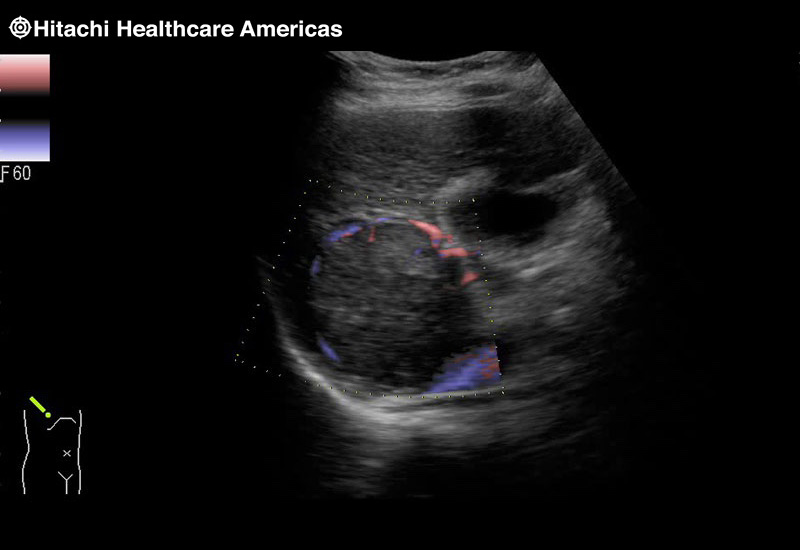

Superior guidance for all applications

Fujifilm Healthcare Americas is committed to designing tools that help surgeons navigate inside the human body and provide the necessary information to immediately make critical surgical decisions.

Fujifilm Healthcare's dedication to Surgeons provides outstanding ultrasound technology, professional support and the specialized tools necessary to best perform comprehensive real-time ultrasound imaging in Breast Surgery, General Surgery, Laparoscopic Surgery, Neurosurgery, Robotic Surgery and Surgical Oncology.

Recognized for our outstanding image quality, outstanding system reliability and intuitive use of cutting edge technology, Fujifilm Healthcare remains the standard in the field of Surgery.

Recognized for our outstanding image quality, outstanding system reliability and intuitive use of cutting edge technology, Fujifilm Healthcare remains the standard in the field of Surgery.